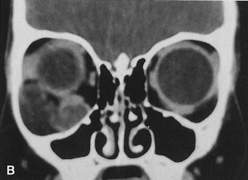

Fig. 16. A. Patient with right orbital cellulitis. B. Coronal CT scan demonstrating subperiosteal abscess formation from frontal and ethmoidal sinusitis. C. Frontoethmoidal orbitotomy incision marked for abscess drainage.

The periosteum is exposed and incised with a Freer elevator and then is reflected off the bone posteriorly. It is generally quite adherent to the curved contour of the medial canthal bones, especially at the medial canthal tendon. The anterior lacrimal crest is encountered inferiorly. Care should be taken not to damage the lacrimal sac with the elevator. The posterior lacrimal crest is visible behind the sac. Adequate mobilization of the periosteal connections to the anterior lacrimal crest gives a large area of exposure. The periosteal elevation is carried superiorly in the area of the trochlea. Elevation of the periosteum opens the subperiosteal space. Blood or pus caused by fracture or infection, if present in this space, is encountered at this point.

Elevation of the periorbita along the medial orbital wall posterior to the lacrimal sac progresses easily. Orbital fractures involving the thin ethmoid bone are seen at this point. The anterior ethmoidal artery is seen at the junction of the ethmoidal and frontal bones where the orbital roof meets the medial orbital wall (see Fig. 7). Usually it is found on a line extending posteriorly from the superior border of the medial canthal tendon. This artery either should be thoroughly cauterized with the bipolar cautery or clipped with a vascular clip before cutting. As the dissection in the subperiosteal space moves posteriorly, the orbit narrows. The posterior ethmoidal artery is identified. This is a reliable landmark for the optic foramen, which lies approximately 5 mm behind the ethmoidal artery.

Indications

The frontoethmoidal medial orbitotomy allows access for a variety of procedures in the subperiosteal and peripheral surgical spaces and sinuses (Fig. 17). Its main use is for processes involving both the frontal or ethmoid sinuses and the orbit. Entrance into the subperiosteal space is obtained easily. Drainage of subperiosteal blood or pus occurs as the space is entered.

Fig. 17. Schematic demonstration of areas amenable to frontoethmoidal orbitotomy. Coronal (A) and axial (B) views. This approach can be used for exposure of the medial orbit, ethmoid and sphenoid sinuses, and optic canal.